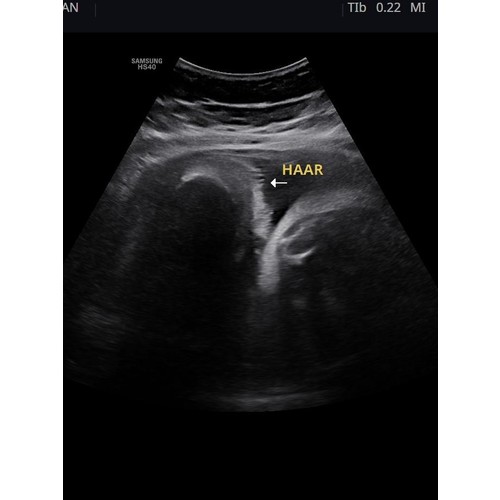

Zeker! Bij ons werd van 30 weken bij de echo's gezegd dat hij een hele bos haar had en dat heeft hij inderdaad ook 😄

Dat kan😄 was bij ons goed te zien

Ja zeker! Was bij ons goed te zien

Ja bij mijn meisje zagen ze een paar plukjes bij de oren🥰

Ja, zowel bij de echo van 24W en 28W was het allebei goed te zien 😊 dus ben eens benieuwd!

Ja ons meisje laat op de echo steeds een wapperend bosje haar zien in t water😍

ja bij ons vanaf 30 weken te zien, ze is ook geboren met een flinke bos haar!

Ja hoor, hier was een duidelijke bos haar te zien haha.

Ja zeker! Dit was met 29 weken. Veel haar kregen wij te horen 😃

Wij kregen ook te horen dat het een bos haar heeft, echo van 34 weken 😊

Bij mij zagen ze haartjes bij de 33 weken groeiecho. 🤗